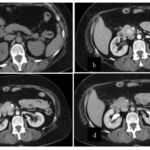

Tomografía de abdomen y pelvis con cte ev: del 13/10/2023.

Complicaciones posquirúrgicas

Tomografía de abdomen con cte ev: del 20/10/2023.

Tomografía de abdomen con cte ev: del 26/10/2023.

Estudio histopatológico reveló neoplásica de estirpe neuroendocrina bien delimitada.